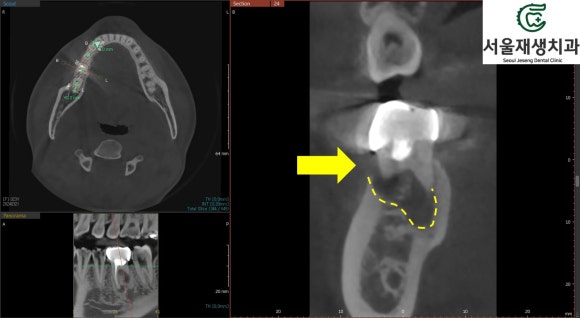

CT 촬영

염증이 몹시 커서

인접 해부학적 구조물과의

연관성을 평가해야 하거나,

위 사례처럼 접근이 어려운 신경의

위치를 파악하기 위해 CT를 촬영합니다.

신경치료 중의 CT 촬영은 대개

건강보험이 적용되어 본인 부담금은 2만원 전후에 불과합니다.

CT를 확인해보니,

치근단염증이 점점 퍼져서

잇몸뼈를 뚫고 나간 것이 보입니다.

그것이 마치 여드름처럼

잇몸으로 불거져 나오는 것이지요.